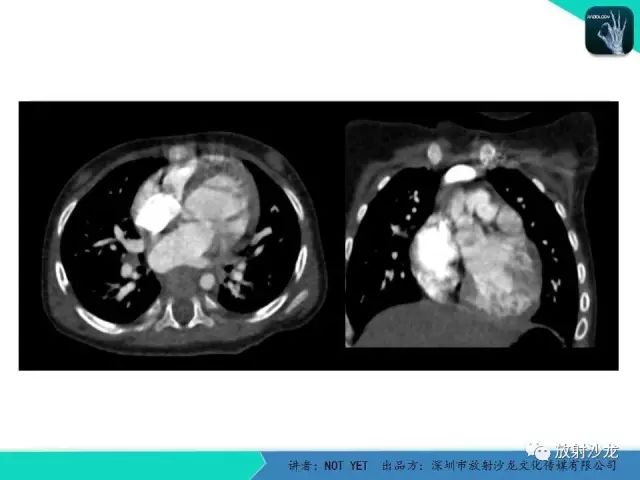

动脉导管未闭1例CT影像表现

【病例】动脉导管未闭1例CT影像表现